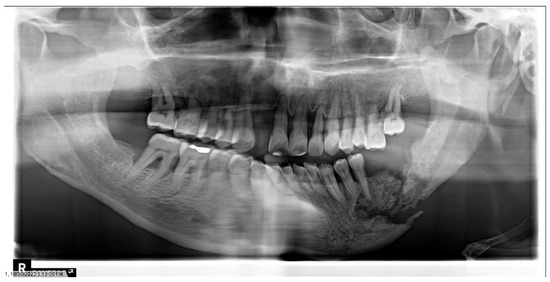

1.2. Trismus

Prevention and Management of Trismus